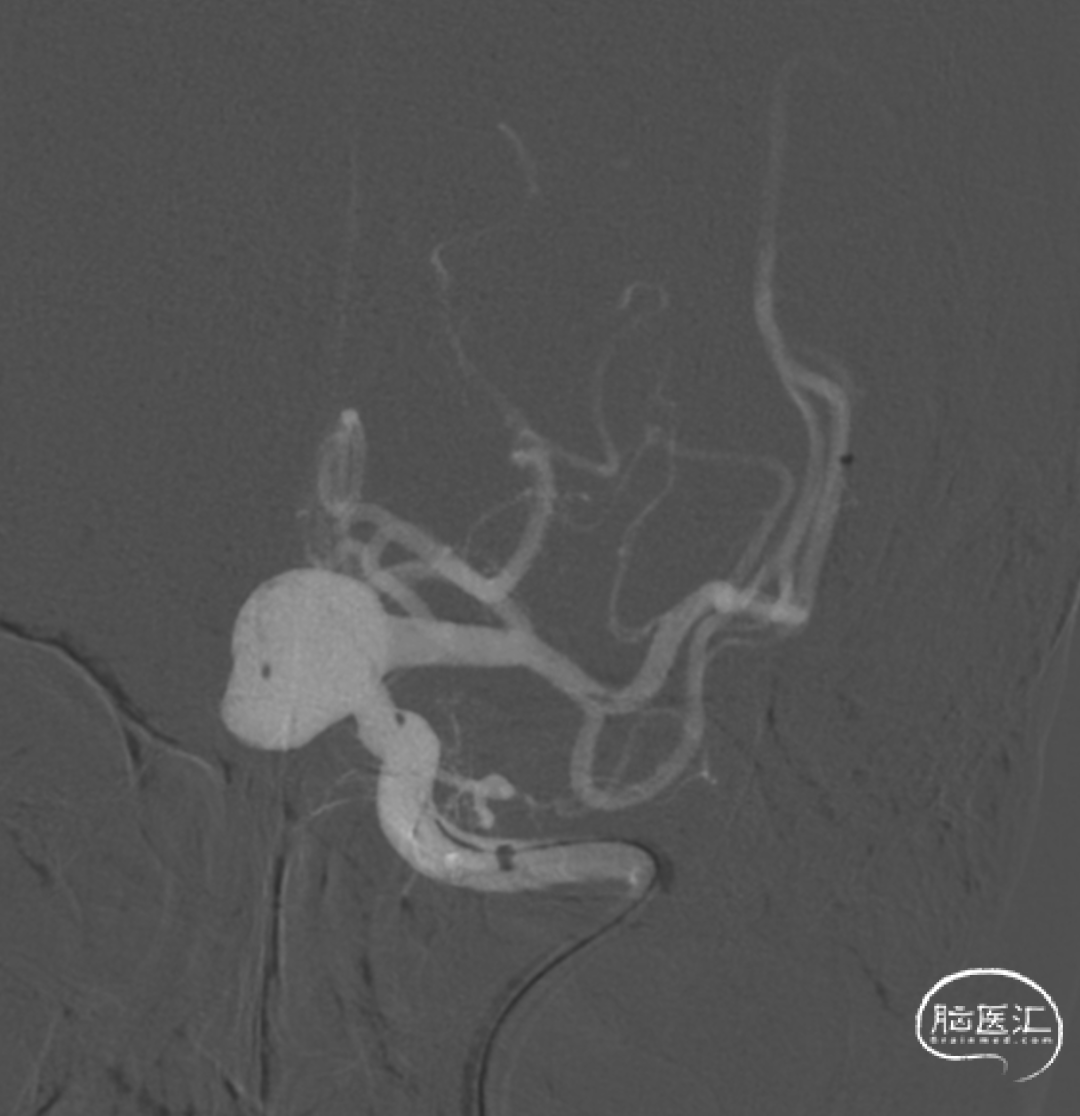

DSA下左侧颈内动脉床突段动脉瘤样染色,呈不规则囊状,瘤体大小约16.6x13.1mm,瘤颈宽6.2mm,载瘤动脉远/近端直径为2.8/4.6mm。

左侧颈内动脉床突段动脉瘤。

颈内动脉⼤型宽颈未破裂动脉瘤,⾸先考虑使⽤FD,本病例相对简单,动脉瘤远端颈内动脉锚定距离较为充分,注意不要覆盖A1即可。动脉瘤体积较⼤,术前即有明显的滞留,为避免术后破裂,应予以辅助弹簧圈填塞。